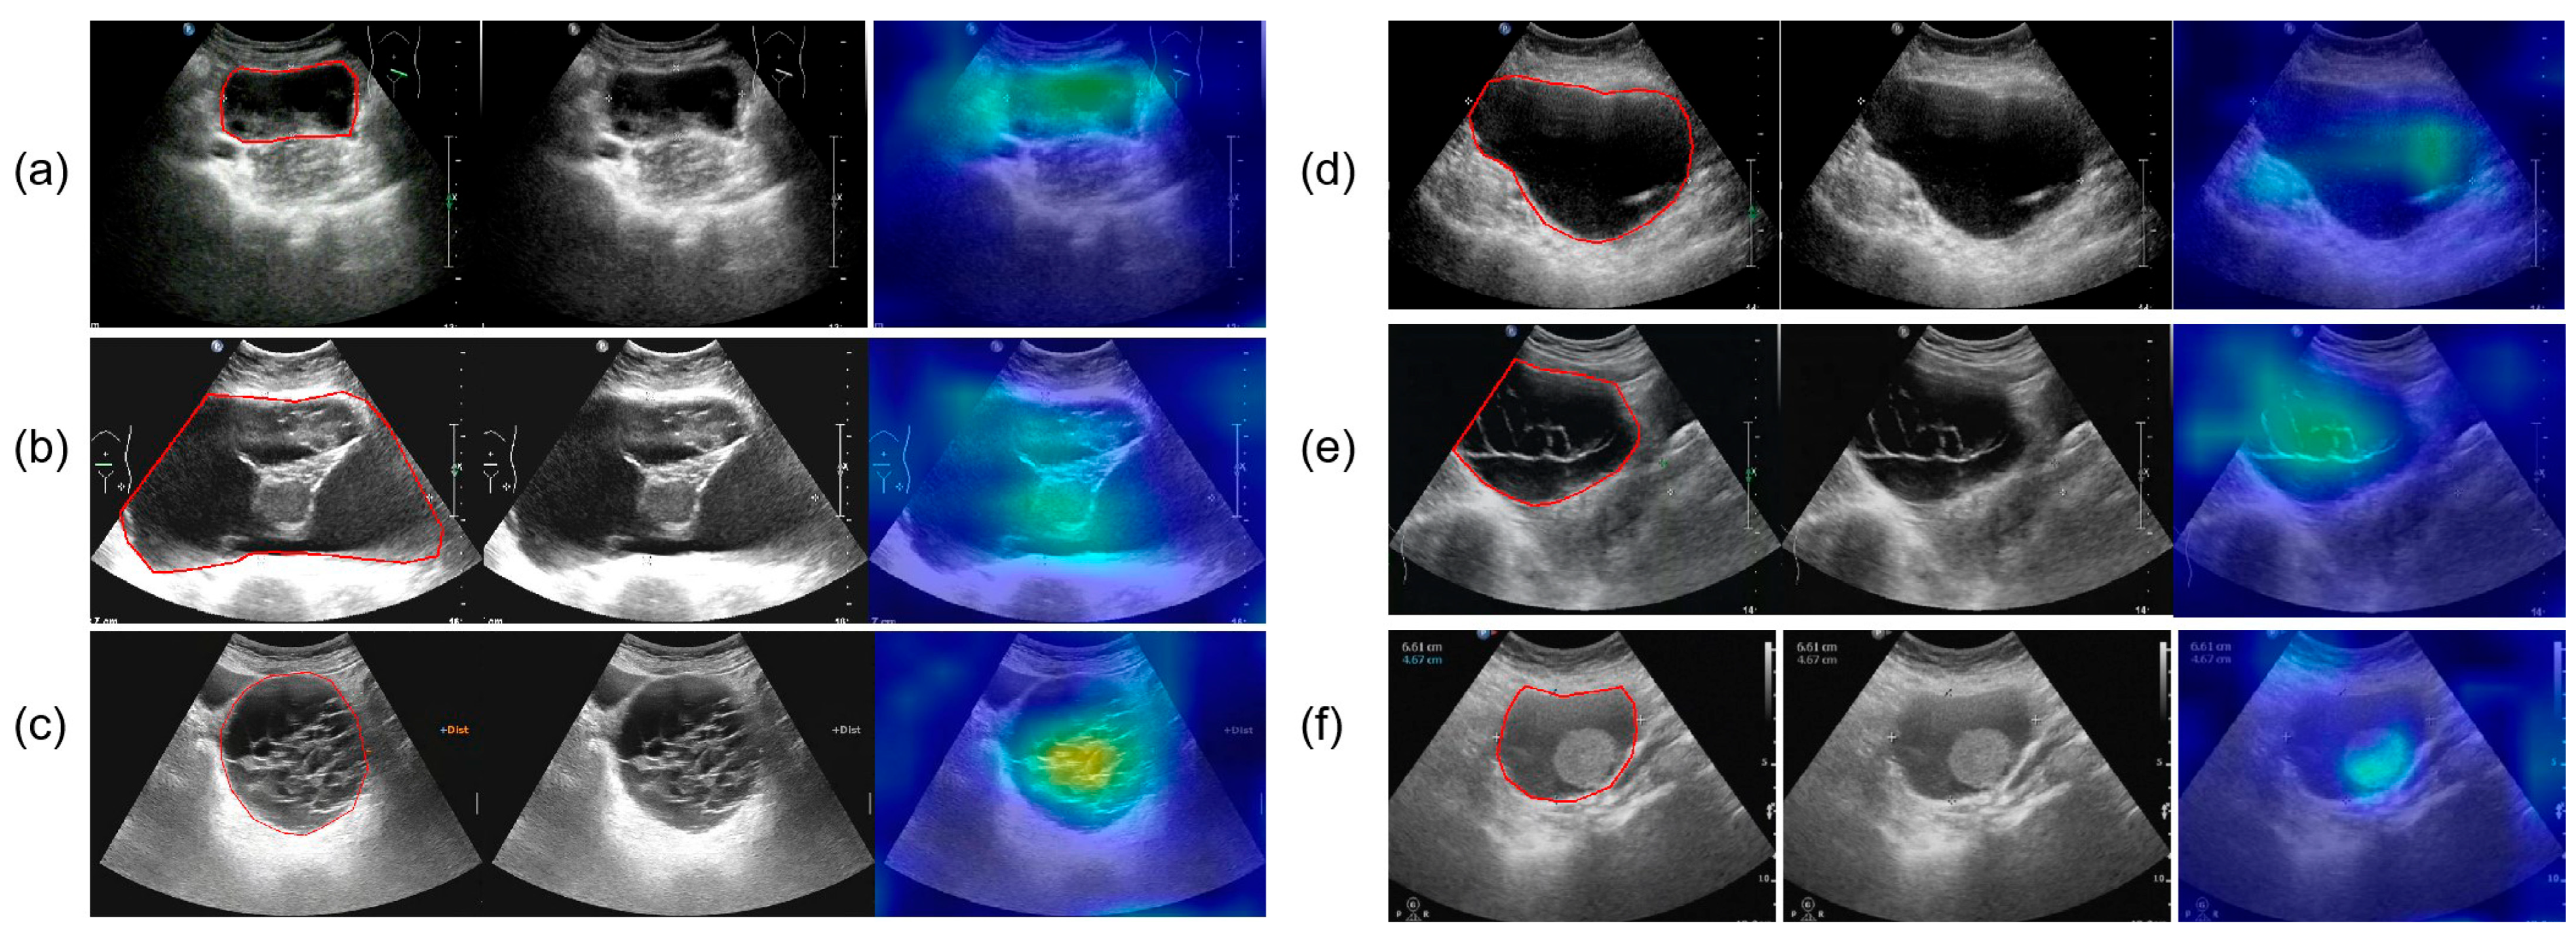

All ultrasound images were obtained from the Picture Archiving and Communication Systems (PACS). Images were acquired using abdominal probes with a frequency range of 1–6 MHz and transvaginal probes with a frequency range of 2–9 MHz. For each patient, the images representing the largest lesion diameter and most complex morphology were selected. Figure 2 provides representative examples of selected cases from this study. Senior radiologists precisely annotated tumor location and boundaries using the Labelme tool (Version 4.5.9, Cambridge, MA, USA) [18]. The lesion regions were then manually cropped and saved as separate images, which were converted to grayscale to standardize the input format for model training.

Figure 2.

The parts circled in red in the image represent the lesions we labelled. (a) A 42-year-old patient with a serous cystadenoma. (b) A 35-year-old patient with a mature cystic teratoma. (c) A 48-year-old patient with a borderline mucinous tumor. (d) A 52-year-old patient with high-grade serous adenocarcinoma. (e) A 65-year-old patient diagnosed with an ovarian fibroma; (f) A 48-year-old patient with an adult-type granulosa cell tumor.